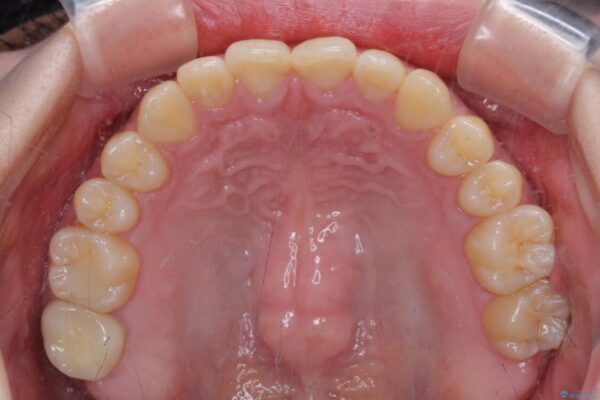

根管治療された歯に症状はなく、オールセラミッククラウンにて補綴治療を行うこととしました。

クラウンはよりよい咬み合わせで装着したいため、インビザラインを1セット使用して概ね歯列を整えた時点で補綴治療を行い、その後仕上げの矯正治療を行いました。

治療後

• 治療途中の奥歯と矯正治療の後戻り インビザライン・ライトによる矯正治療 治療後画像